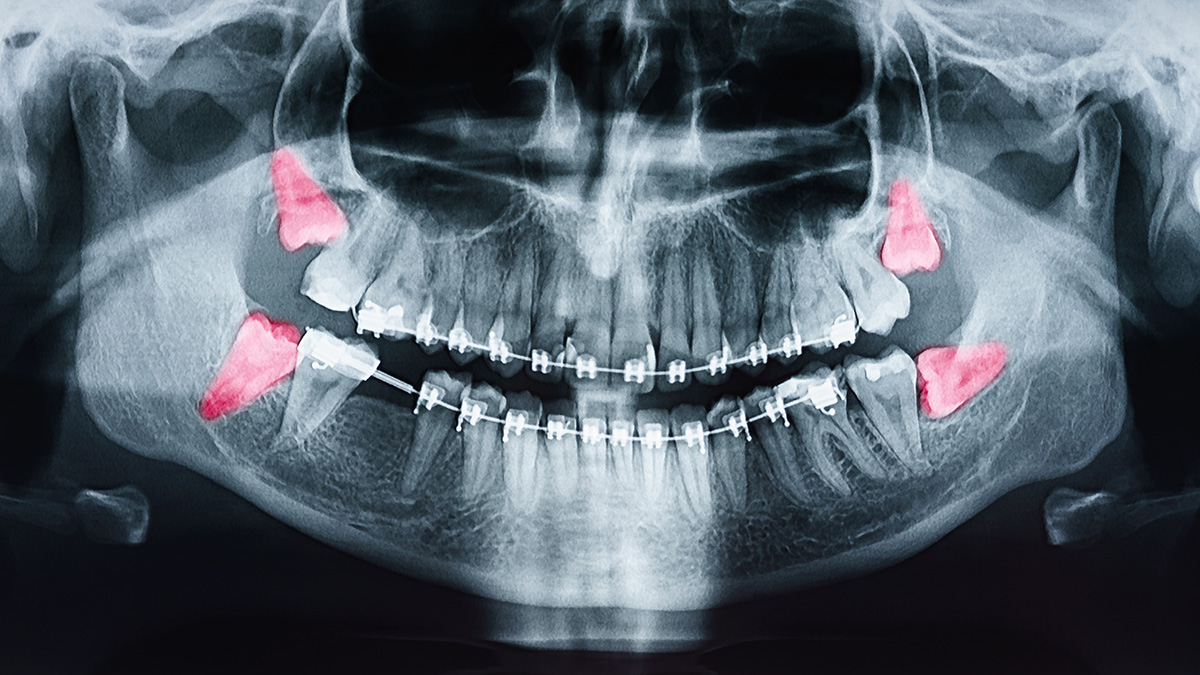

The most common reason for wisdom teeth extractions is insufficient space in the mouth. When there is not enough room for the wisdom teeth to emerge properly, they may become impacted, meaning they cannot fully break through the gum line. Impacted wisdom teeth can lead to various issues, including pain, infection, and damage to neighboring teeth.

Wisdom teeth may erupt at awkward angles or positions, causing them to press against neighboring teeth. This misalignment can result in crowding and disrupt the alignment of your existing teeth.

A fluid-filled sac may sometimes form around the impacted wisdom tooth, resulting in a cyst. Cysts can damage the surrounding bone and teeth and require surgical removal.